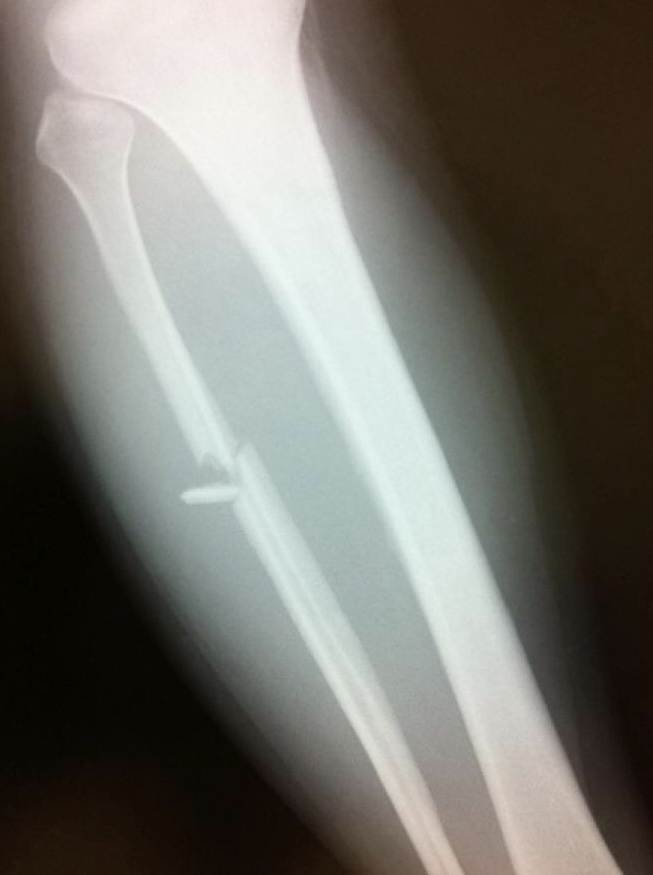

2011年11月、やっと仙台で興行が出来そうな矢先に足の腓骨を折った。

半年間痛みに耐えて試合に出続けた。